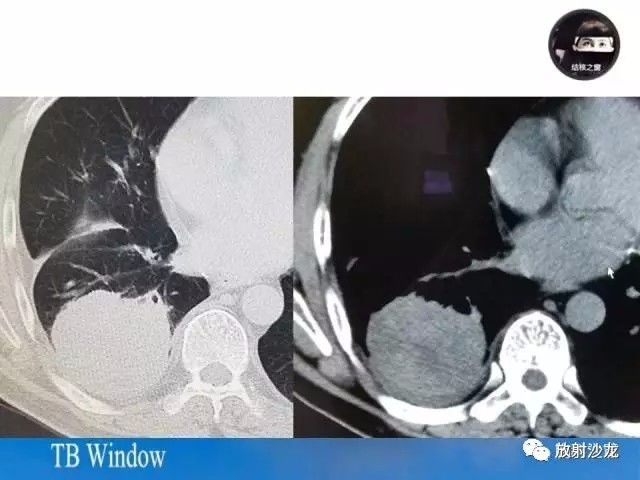

【PPT】周围型肺鳞癌的影像征象及鉴别诊断